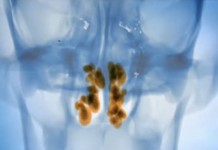

Эндоскопическое лечение гайморита

В операционной телевизионной клиники программы "Здоровье" при помощи крошечной телекамеры хирурги проведут совершенно безболезненную процедуру и избавят пациентку от гайморита.